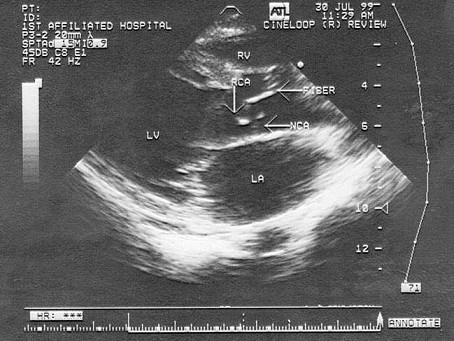

该病例最可能诊断?(?)A.主动脉瓣钙化B.先天性主动脉瓣畸形(二叶式)C.风湿性瓣膜病D.主动脉瓣脱垂E.主动脉窦瘤

问题 该病例最可能诊断?(?)

选项 A.主动脉瓣钙化 B.先天性主动脉瓣畸形(二叶式) C.风湿性瓣膜病 D.主动脉瓣脱垂 E.主动脉窦瘤

答案 B